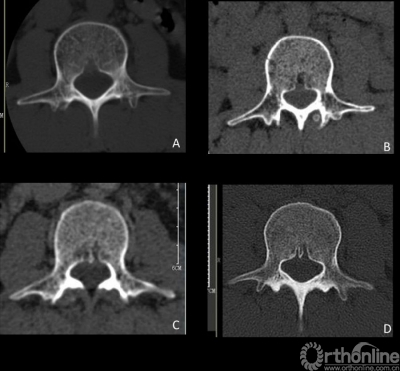

结果显示,①形状上:共分为3种类型(图5):三角型(65%)、梯型(24%)、不规则型(11%),其中不规则型中6%BF内部出现骨性间隔。②尺寸上:椎基静脉孔平均高度为9.2±2.5mm,平均深度是4.4±1.6mm。相同测量节段的BFW、BFD和BFH最大值接近或超过同一测量平面椎体宽、深和高的1/3,平均宽、深和高接近或超过同一测量平面椎体的25%。③位置上:与下终板相比,椎基静脉孔更接近上终板。另外BF在不同个体的物理参数存在较大差异,受年龄、性别、体重指数等影响。年龄是各因素中权重最高的,随着年龄增大,BF的高度变大,深度变浅。女性腰椎的BF高度和深度相对较大。重体力劳动者可导致BF高度降低。

图5 椎基静脉孔不同形状分型。A 三角型;B梯型;C不规则型;D不规则型中特殊类型之骨间隔型